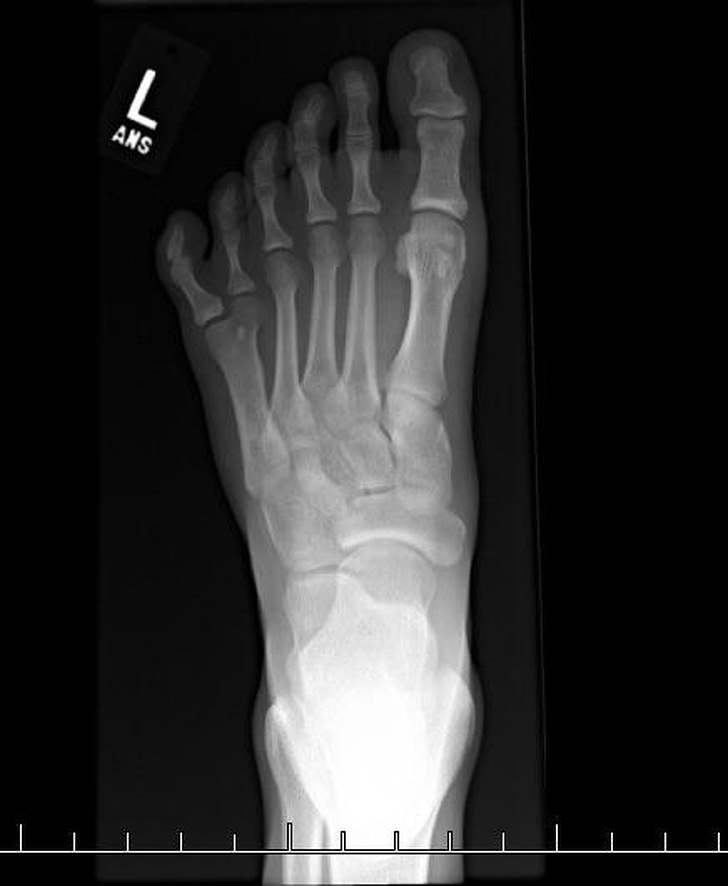

12. Так виглядають шість пальців на рентгені